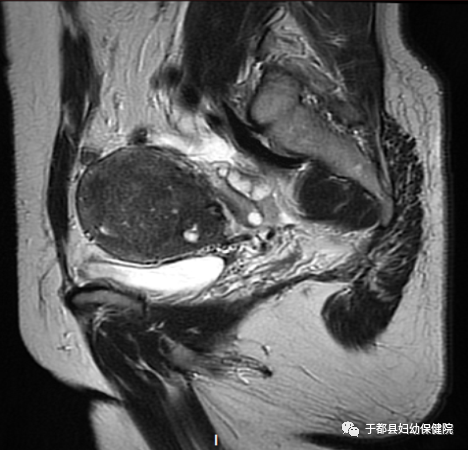

卵巢肿瘤、卵巢癌:

有利于肿块的发现、来源的判断及组织成分的确定,从而有助于肿块的定性诊断,另外还能发现腹水、腹腔的种植性转移、淋巴结转移和邻近结构的直接侵犯。